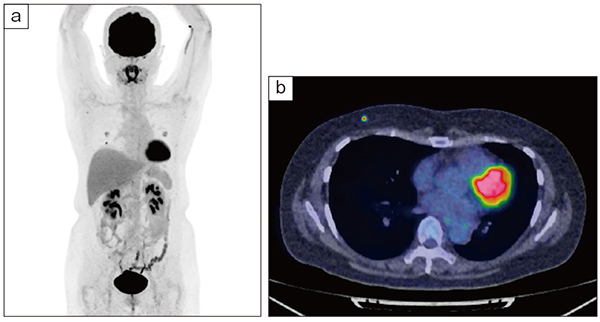

図2 FDG-PET

a:MIP画像

b:fusion(axial)画像